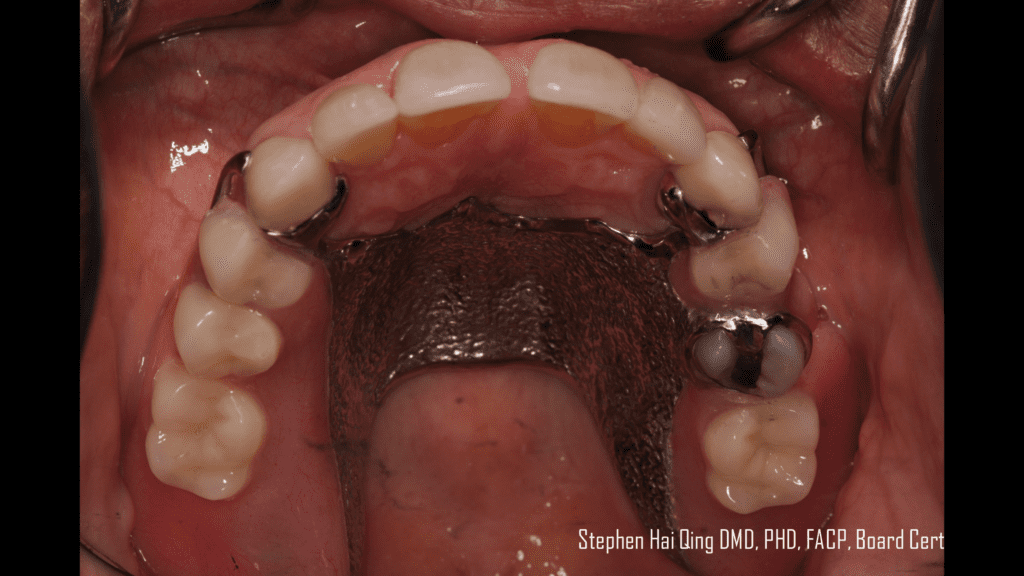

Esthetic Removable Partial Denture Posted by inception1 on August 23, 2022, 05:07 AM Esthetic Removable Partial Denture SHARE THIS POST:Share on X (Twitter)Share on FacebookShare on PinterestShare on LinkedInShare on Email « Previous Post Next Post »